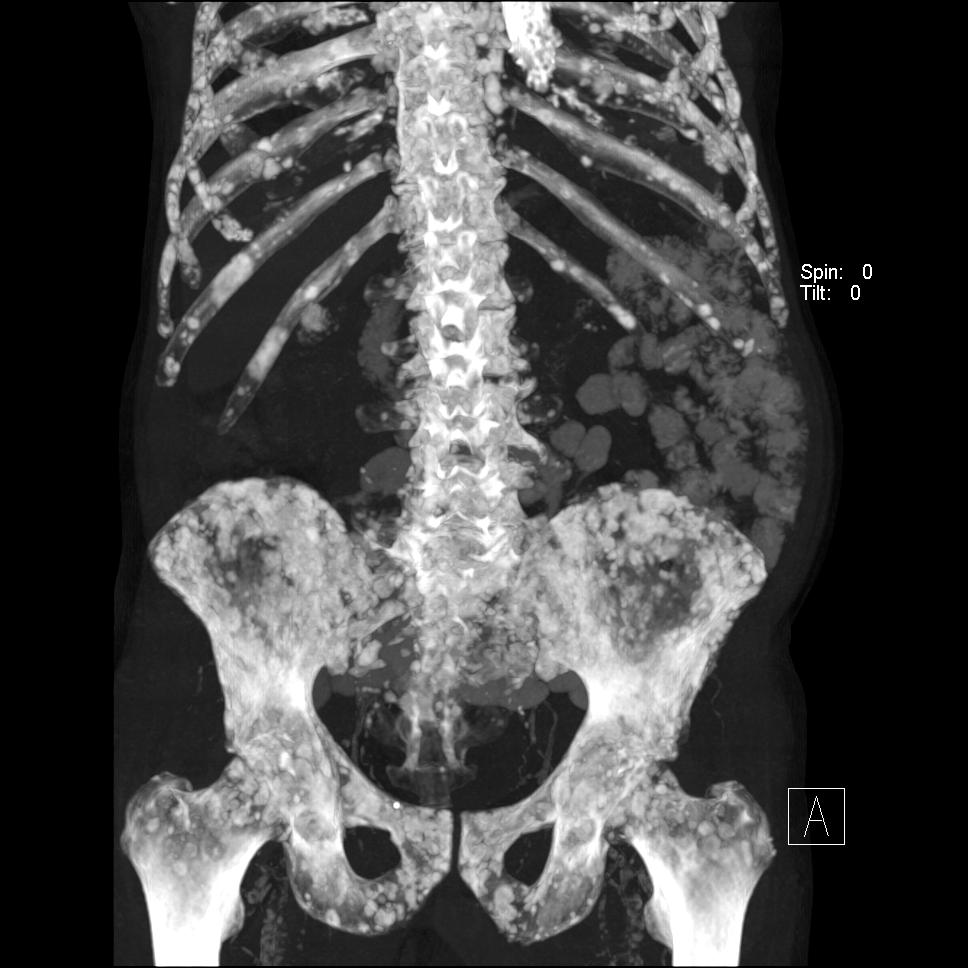

- Diffuse skeletal

- Oncohaematology